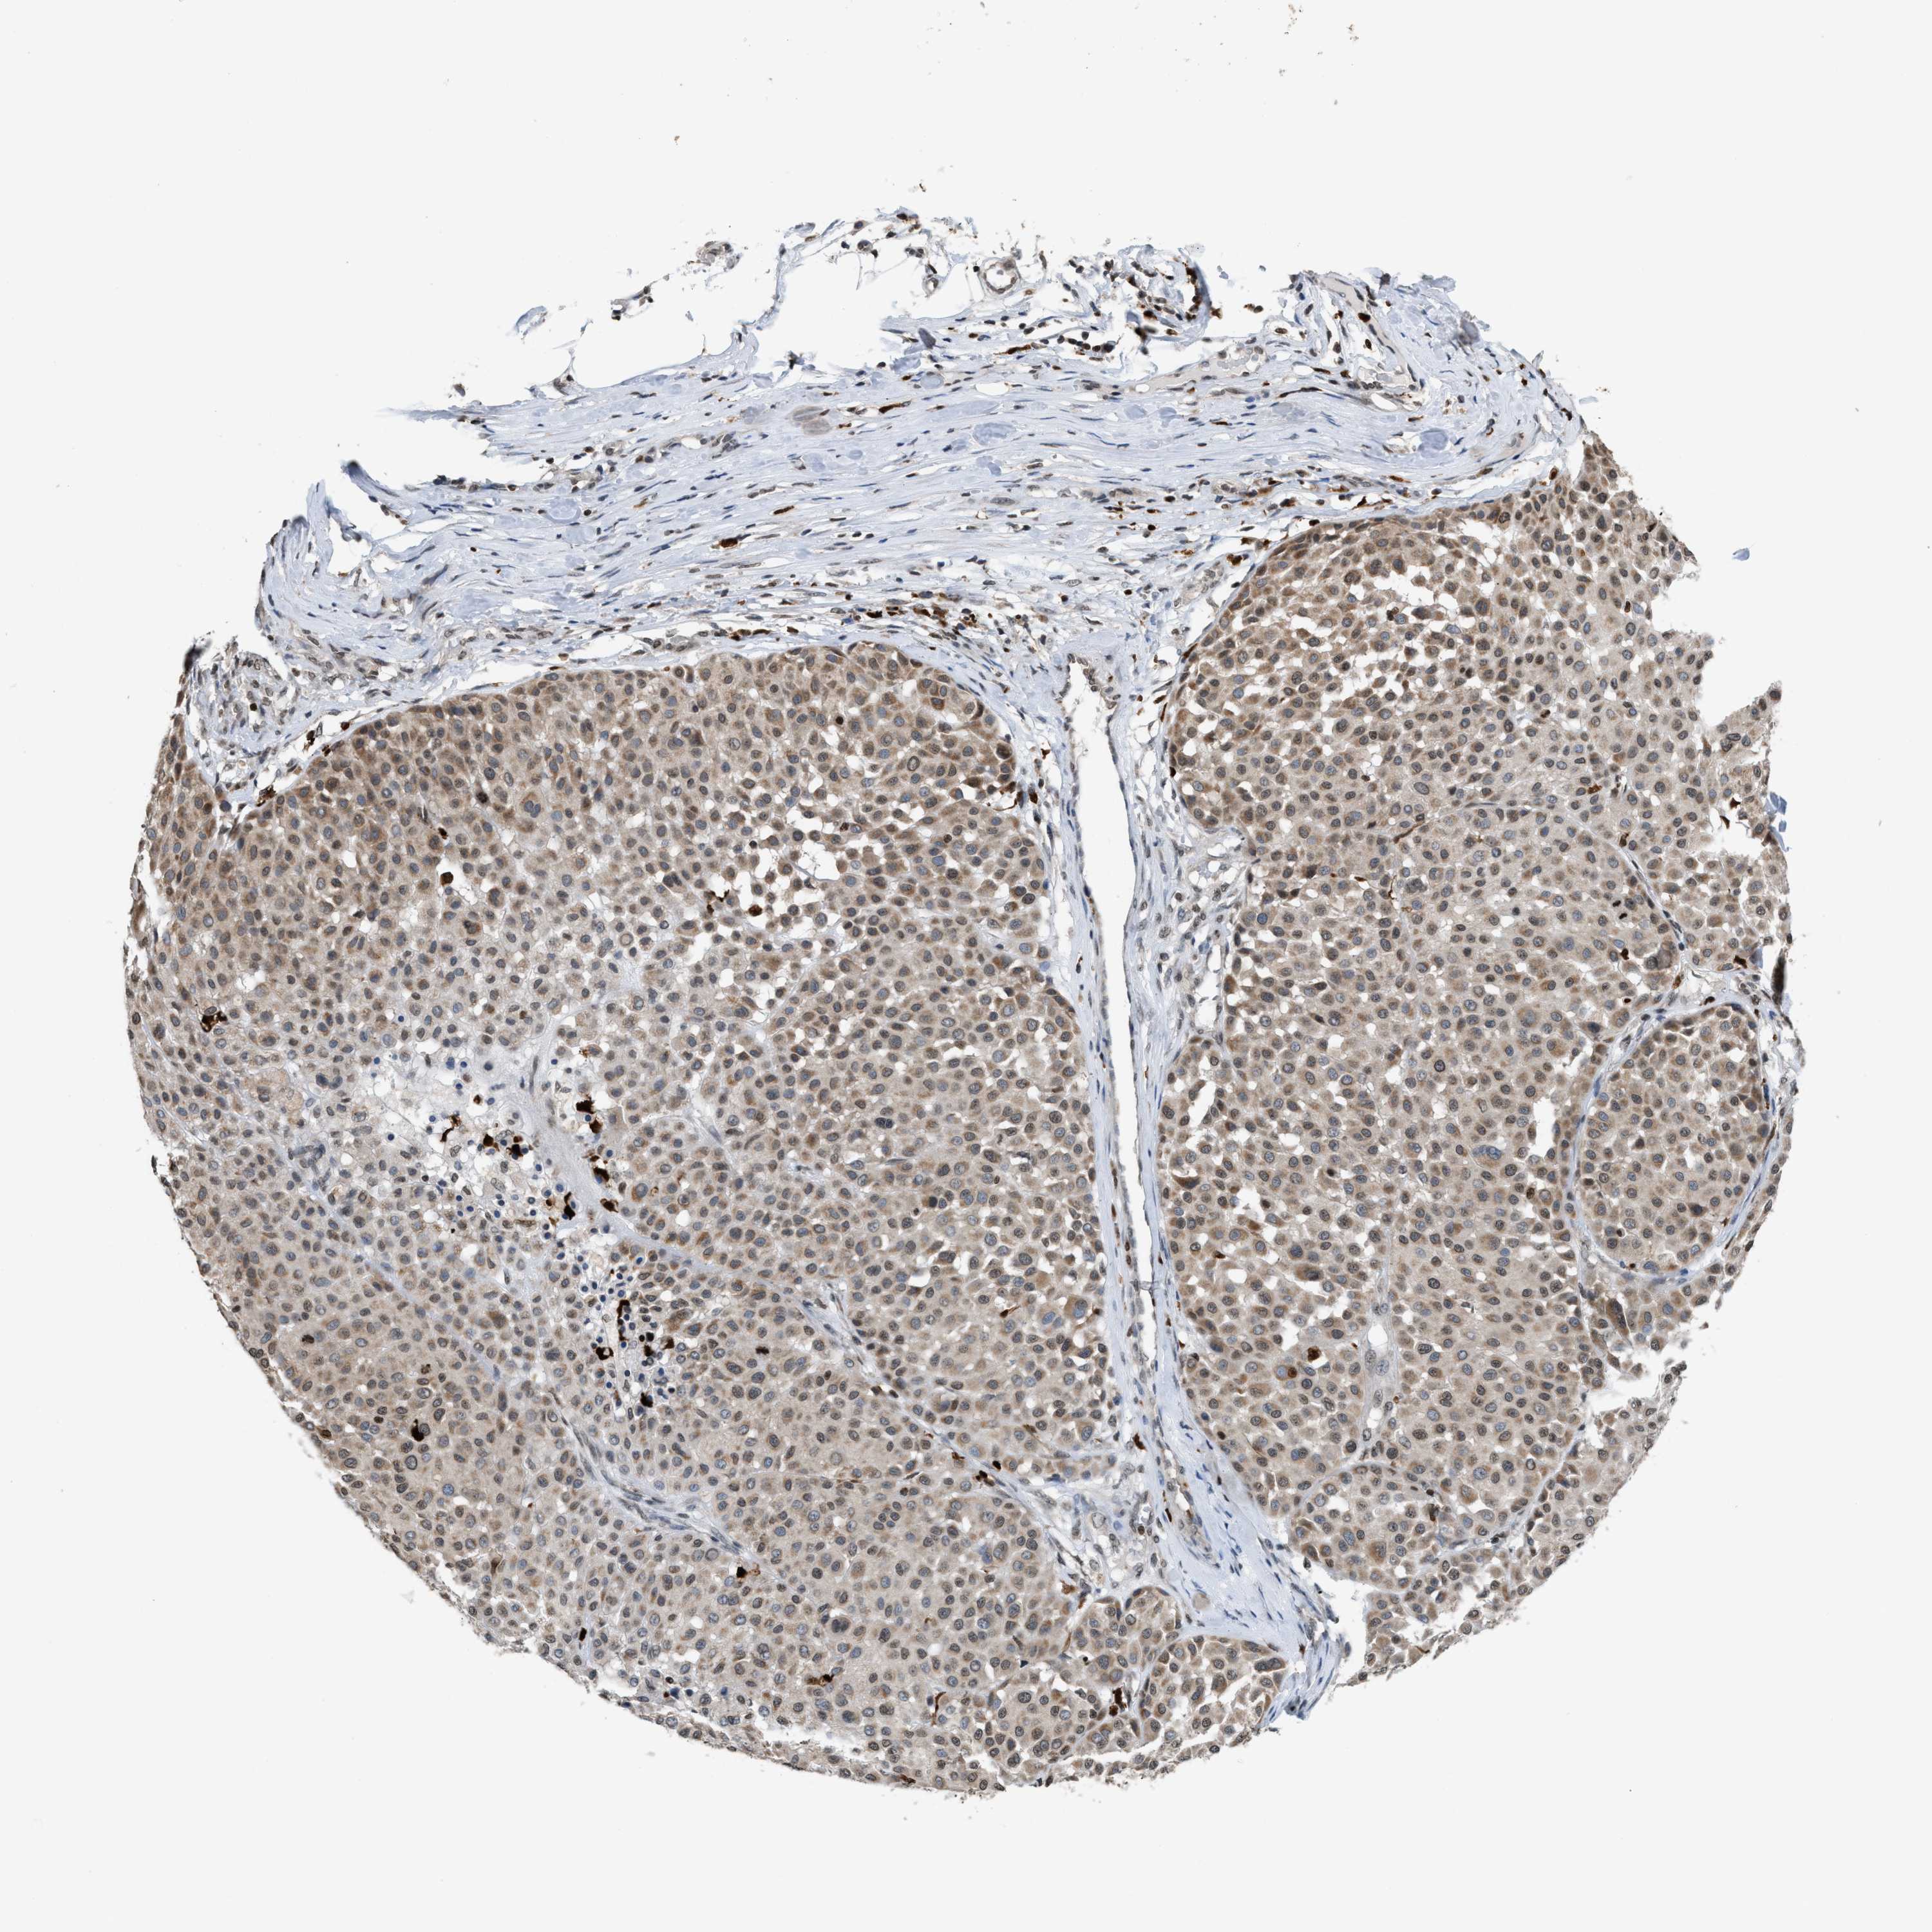

MELANOMA - Protein expressioni

A mouse-over function shows sample information and annotation data. Click on an image to view it in a full screen mode. Samples can be filtered based on level of antibody staining by selecting one or several of the following categories: high, medium, low and not detected. The assay and annotation is described here.

Note that samples used for immunohistochemistry by the Human Protein Atlas do not correspond to samples in the TCGA dataset.

Antibody stainingi

Antibody staining in the annotated cell types in the current human tissue is reported as not detected, low, medium, or high, based on conventional immunohistochemistry profiling in selected tissues. This score is based on the combination of the staining intensity and fraction of stained cells.

Each image is clickable and will lead to virtual microscopy that enables deeper exploration of all samples and also displays staining intensity scores, fraction scores and subcellular localization as well as patient and tissue information for each sample.

Antibody HPA022470

Antibody HPA031079

Staining

High

Medium

Low

Not detected

Intensity

Strong

Moderate

Weak

Negative

Quantity

>75%

75%-25%

<25%

None

Location

Nuclear

Cytoplasmic/membranous

Cytoplasmic/membranous,nuclear

Malignant melanoma, NOS

Malignant melanoma, Metastatic site